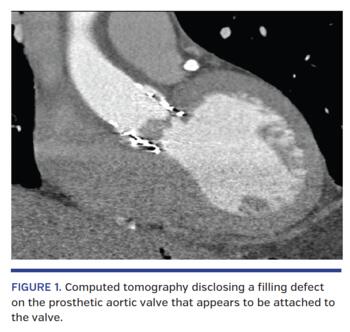

An 86-year-old man with a history of transcutaneous aortic valve implantation (TAVI) 2 years prior to his admission was admitted to our hospital due to weakness and low-grade fever for 1 week. The patient was known to have a higher than normal pressure gradient post TAVI and received anticoagulation for the last year due to suspected post-TAVI valve thrombosis. Two months prior to his admission, the patient was diagnosed at another medical center with bacterial endocarditis of his prosthetic aortic valve, after blood cultures were positive for Enterococcus faecalis. The patient was treated for 4 weeks with daptomycin and was considered disease free. Upon admission to our center, the patient exhibited a third-degree (complete) atrioventricular block on electrocardiogram. The patient was hemodynamically stable and did not require transcutaneous pacing or inotropic support. Echocardiography showed high pressure gradients (100 mm Hg) on the aortic valve, and suspected thrombus or vegetation on the aortic valve. A computed tomography scan with intravenous contrast was performed, showing a large filling defect on the prosthetic aortic valve (Figure 1). Blood cultures drawn at the patient’s admission returned positive for the same Enterococcus faecalis grown at the prior admission. The patient was suspected to have an infected thrombus on a TAVI valve and was referred to urgent surgery. The valve with the infected thrombus (Figure 2) was removed and a biological prosthetic valve was implanted in its place. The procedure and its postprocedural course were uneventful.